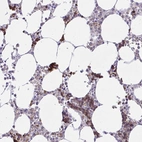

Immunohistochemical staining of human bone marrow shows strong cytoplasmic positivity in hematopoietic cells.